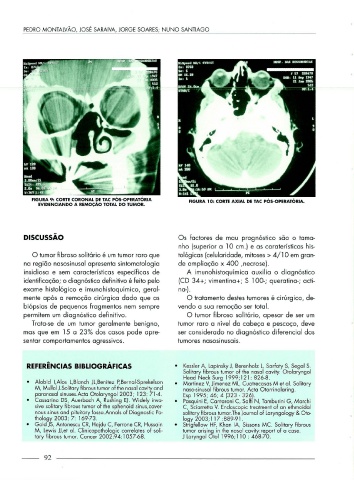

FIGURA 9: CORTE CORONAL DE TAC PÓS-OPERATÓRIA FIGURA 10: CORTE AXIAL DE TAC PÓS-OPERATÓRIA.

EVIDENCIANDO A REMOÇÃO TOTAL DO TUMOR.